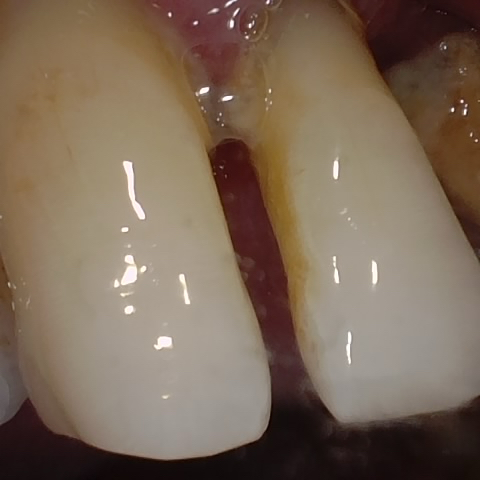

Annotated as "Bad"